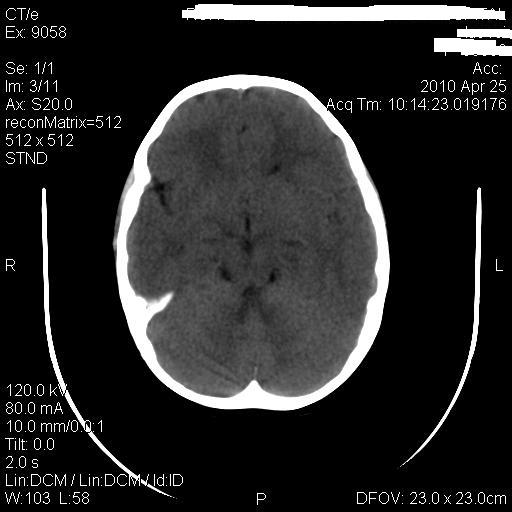

标题: PED3218:3岁女孩,曾有外伤史。未提供前片 [打印本页]

标题: PED3218:3岁女孩,曾有外伤史。未提供前片

发育略有障碍。欢迎大家发言。谢谢!

考虑右侧额顶叶脑软化灶并脑穿通畸形。

有无胼胝体发育不良?

考虑:1)右侧额顶叶脑软化灶并脑穿通畸形。2)胼胝体发育不良。

1)右侧额顶叶脑软化灶。2)胼胝体发育不良?

考虑右侧额顶叶软化灶并脑穿通畸形,胼胝体发育不全。

支持考虑:1)右侧额顶叶脑软化灶并脑穿通畸形。2)胼胝体发育不良。

还有脑室周围白质软化症